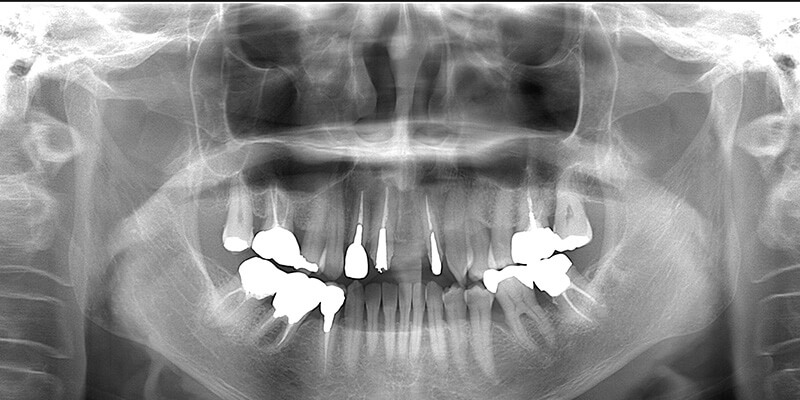

| 診査診断 | 上顎歯牙欠損、歯周病、不良補綴、根尖性周囲炎。 不正咬合により噛み合わせのバランスが悪い事が原因により咬合治療が必要。 |

| 治療内容 | 欠損部インプラント 不正咬合に対し不良補綴のやり直しと合わせて咬合再構築 |

| 治療期間 | 4ヶ月 |

| 費用 | 200万円 |

| 診査診断 | 歯周病、歯の崩壊、不良補綴。 全顎的咬合異常、前歯の噛み合わせ、奥歯の噛み合わせに問題あり。 |

| 治療計画 | 欠損部インプラント 不良補綴のやり直しと欠損部インプラント。 咬合の再構築、なるべく歯を残せる様に治療計画を立案。 |

| 治療期間 | 6ヶ月 |

| 費用 | 290万円 |